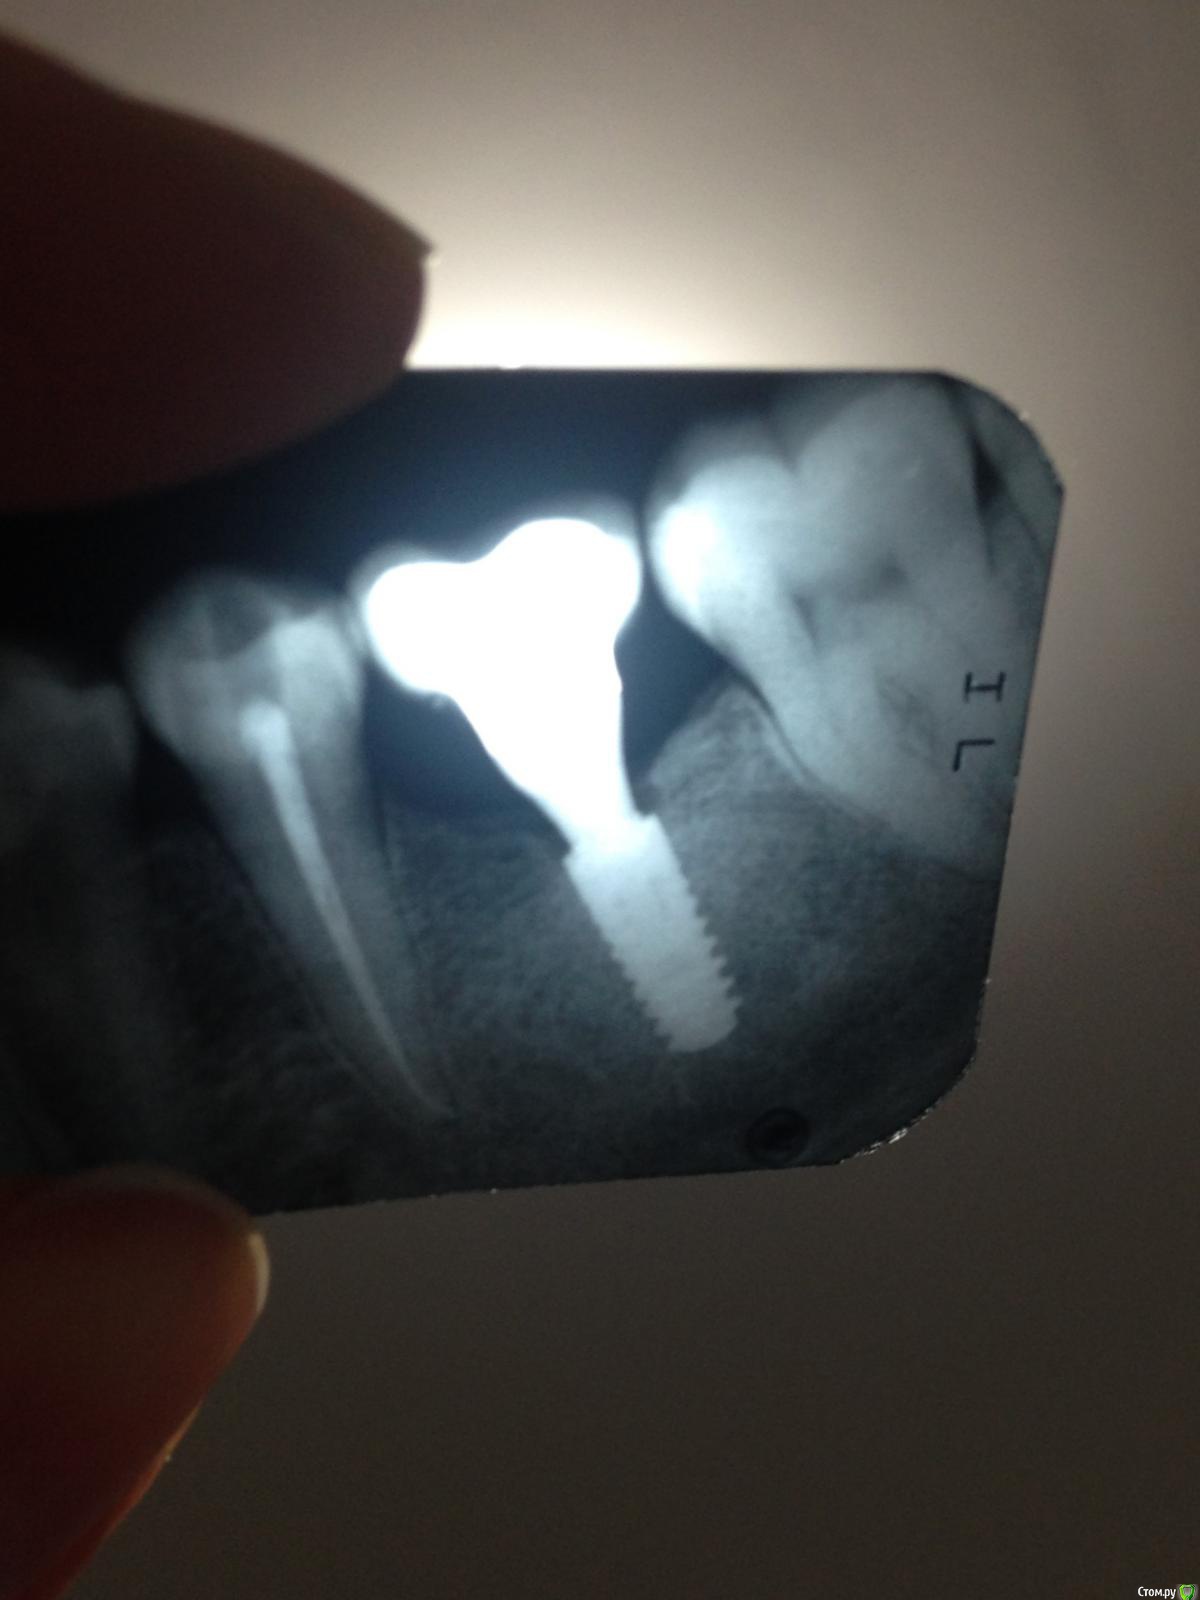

Ирина А. Опубликовано 12 мая, 2016 Поделиться Опубликовано 12 мая, 2016 (изменено) Добрый день, уважаемые доктора!Вопрос по лечению оголения импланта: стоит лет 5-6, изначально проявилась убыль костной ткани, но в последнее время несколько больше оголился имплант и я стала переживать за соседние зубы, так же появился дискомфорт, так как ощущается даже щекой с закрытым ртом, что есть пустое пространство в районе импланта.Хотелось бы найти грамотного специалиста, способного решить проблему.И узнать варианты решения)Извините за качество фото)Спасибо! Изменено 12 мая, 2016 пользователем Ирина А. Ссылка на комментарий

Aquarius Опубликовано 12 мая, 2016 Поделиться Опубликовано 12 мая, 2016 похоже, что цемент под десной, недостаток кератинизированнных тканей, как следствие - хроническое воспаление. 1 Ссылка на комментарий